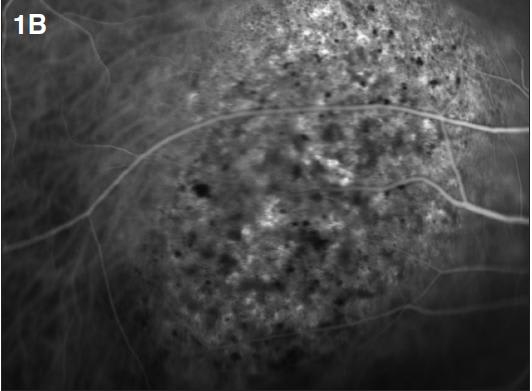

Indocyanine green demonstrates specific angiographic features, including early hyperfluorescence (Figure 1b), followed by late hypofluorescence (washout of dye) and a hyperfluorescent rim (Figure 1c).2

Figure 1. Circumscribed choroidal hemangioma. A 45-year-old female presented with reduced vision in the right eye (20/40). A fundus exam revealed a dome-shaped choroidal mass (A). ICG demonstrated early hyperfluorescence (B, 1:15 minutes). Note hypofluorescence (washout of dye) with a hyperfluorescent rim in the late phase (C, 12:20 minutes). A dome-shaped choroidal mass with smooth contours was observed on B-scan ultrasonography (D) with high internal reflectivity on A-scan (E). One year after treatment with PDT, fundus evaluation showed a regressed hemangioma (F), which was confirmed on B-scan ultrasonography (G). Visual acuity improved to 20/20.